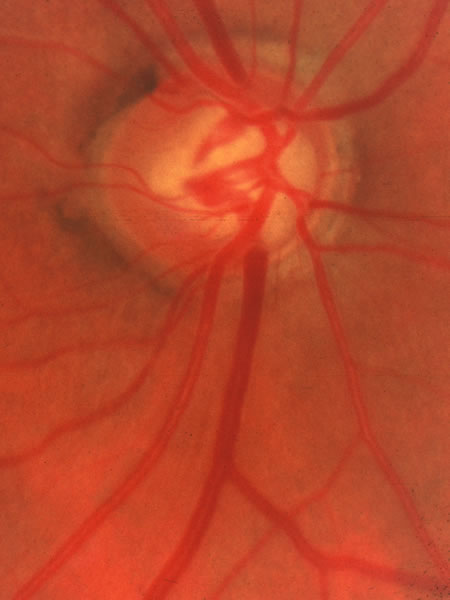

Usually all other forms of optic nerve disease (and inner retinal disease) produce simple atropy of the disc without cupping (Figs. 34 to 36), but occasional cases of cupping have been seen with anterior ischemic optic neuropathy, particularly due to giant cell arteritis (Figs. 37 and 38).

Fig. 34. Photograph of a normal left eye at a time when the right eye had an attack of anterior ischemic optic neuropathy.

Fig. 35. Same eye as Figure 34 during a subsequent attack of ischemic optic neuropathy.

Fig. 36. Same eye as in Figure 34 one year later, with atrophy but no excavation.